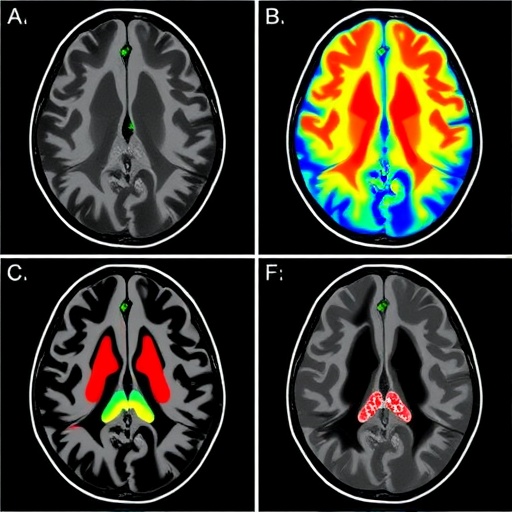

The team employed state-of-the-art phase-contrast MRI protocols, specifically optimized to capture subtle fluid velocities within the cranial cavity. These methods enable a pixel-by-pixel quantification of flow velocities, capturing oscillations synchronous with cardiac activity. This is crucial because heart-driven pulsations are understood to be major contributors to CSF movement, but the regional heterogeneity of their effect had remained elusive until now.

Focusing on a cohort of healthy volunteers, the investigators mapped CSF flow at multiple brain loci, including ventricular spaces, the subarachnoid compartments, and perivascular regions. Their quantitative data revealed that certain compartments exhibit pronounced flow signatures corresponding to cardiac and respiratory cycles, whereas others showed dampened or delayed responses. This spatiotemporal coupling between vascular rhythms and CSF movement offers compelling evidence for localized biomechanical interactions modulating fluid transport.